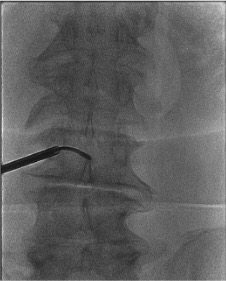

Lateral View โ Depth Control

- Advance trocar to posterior 25% of vertebral body depth on lateral view before inserting curved cannula

- Insert curved cannula through trocar; advance to center of the vertebral body (50% depth) on lateral โ this is the BVF location

- Correct lateral position: tip slightly posterior to true center (posterior 40–50% of body depth)

- Stop immediately if trocar or cannula approaches the anterior 25% on lateral โ risk of anterior cortex breach

- Anterior cortex breach = potential injury to great vessels or viscera โ abort and obtain CT